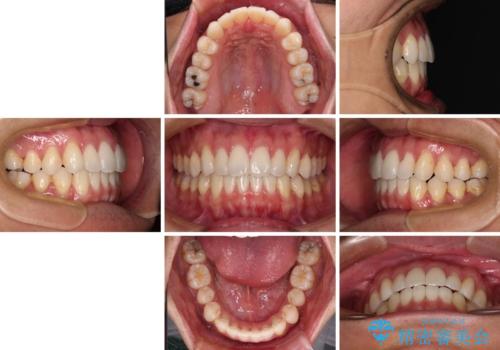

少しでも口元を閉じやすく インビザラインによる前突の解消

- 全体的なデコボコと、前歯の前に出ている感じを気にして来院された患者様です。

患者様と相談の上、非抜歯にてインビザラインを用いて矯正治療を行うこととし、IPR(歯と歯の間)並びに歯列全体の後方移動により口元の突出感の改善することとしました。

お仕事が忙しい方で、装着時間が不足したり、定期的な通院ができなかったりと、自己管理が重要なインビザラインによる矯正治療が長期化する要因が重なり、5年ほどの期間を要しました。